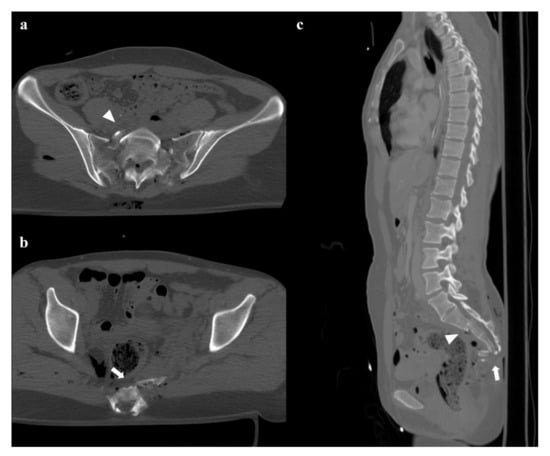

• Grade 1: compression fracture of the sacrum on the side of the impact, and transverse fracture of unilateral or bilateral pubic branches (Figure 1). Lateral compression grade 1 injuries are stable and have a nonoperative management [3].

• Zone II: the fracture involves the neuroforamina (Figure 1). In 28% of cases, there is an ipsilateral neurological deficit.

Figure 1. Lateral compression fracture, type 1. Axial computed tomography (CT) images show a fracture of the right-side superior and inferior pubic rami (arrows in (a,b)), and ipsilateral fracture of the sacrum (arrowheads in (c)); the sacral fracture involves the neuroforamina (zone II). Three-dimensional volume-rendering CT reconstruction in anteroposterior (AP) view confirms the type of fracture (d).